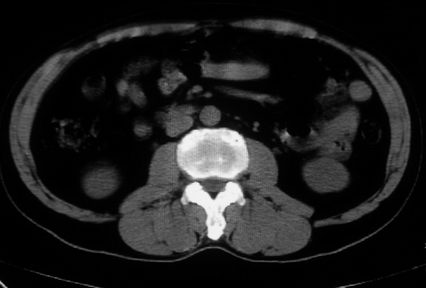

男,体查发现右肝低密度,右肾高密度结节影。高密度ct值92hu,囊肿?

肝右叶囊肿或血管瘤?右肾高密度囊肿。建议增强。

肝右叶圆形低密度灶,考虑囊肿或血管瘤,建议ct增强检查;右肾包膜下高密度圆形灶,考虑:囊肿并出血

考虑肝右叶囊肿,右肾高密度囊肿;建议行ct增强扫描检查。